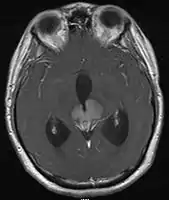

- Mainly located in midline structures, suprasellar region or pineal gland, also basal ganglia and hypothalamus

- Pineal Gland Germinoma

- Suprasellar Germinoma